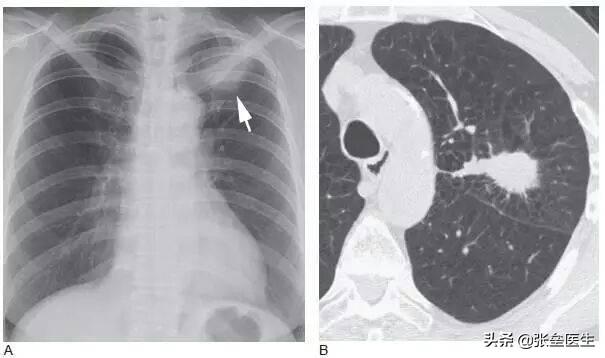

La tomodensitométrie thoracique à faible dose est la méthode la plus efficace pour détecter le cancer du poumon à un stade précoce et peut détecter le cancer du poumon périphérique à un stade précoce.

Pour les personnes présentant un risque élevé de cancer du poumon, il est recommandé de passer un scanner thoracique une fois par an, notamment celles qui ont plus de 50 ans, qui ont une longue histoire de tabagisme ou de tabagisme passif, qui ont des antécédents de cancer du poumon dans la famille ou qui ont des nodules pulmonaires détectés lors d'examens précédents, qui sont exposées à des facteurs cancérigènes sur leur lieu de travail ou de vie, et qui présentent des lésions chroniques répétées aux poumons, telles que des infections récurrentes, la tuberculose, etc. Si vous avez fumé pendant plus de 20 ans et plus d'un paquet par jour, même si vous n'avez pas 50 ans, il est recommandé de passer un scanner thoracique à faible dose une fois par an afin de pouvoir détecter et traiter plus de lésions précoces grâce à un examen physique.